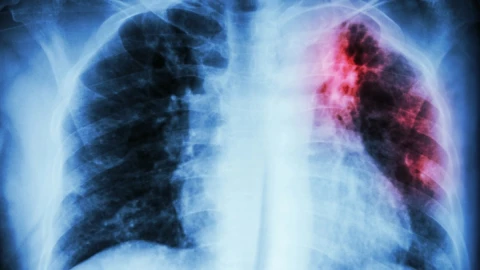

В селе Новоишимское Северо-Казахстанской области у шестиклассника средней школы № 1 выявлена открытая форма туберкулёза. Ребёнок госпитализирован, в образовательном учреждении проведена дезинфекция и продолжается медицинское обследование всех контактных. Родители обеспокоены и просят временно перевести детей на дистанционное обучение, однако школа продолжает работать в обычном режиме.

Как стало известно, заболевший мальчик уже проходил лечение от туберкулёза в 2021-2022 годах. Новый случай — это рецидив.

"12 мая в департамент поступило экстренное извещение из районного управления о том, что выявлен случай заболевания туберкулёзом у ученика 6 класса Новоишимской школы № 1, — сообщил заместитель руководителя департамента санитарно-эпидемиологического контроля Северо-Казахстанской области Арман Кушбасов. — Это рецидив. В 2021 году ребёнок заболел, в 2022 году завершил лечение. Но поскольку в лёгких оставались изменения, риск повторного заболевания сохранялся".